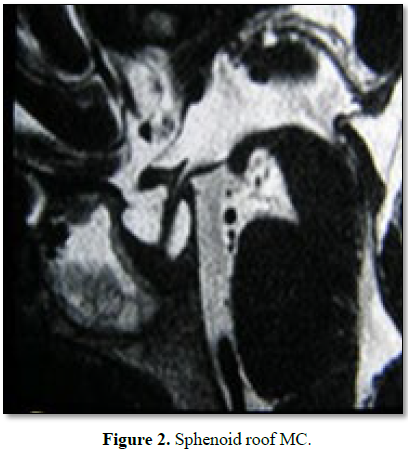

prior MC surgeries. In 2 cases the MC was located in the sphenoid lateral wall (Figures 1A and 1B), one was located in

the sphenoid roof (Figure 2), 2 in

the cribriform plate and one patient, with MEC diagnosis, had it located in the

frontal sinus. 66.6% had anterior rhinorrhoea (4/6) (Table 1).